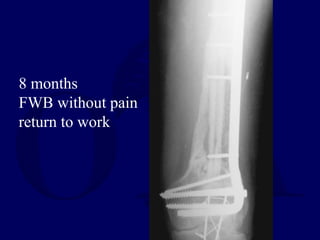

8 months

FWB without pain

return to work

ORIF with bladeplate fibularstrut allograft cancellous autograft CaSO4 pellets Bone stimulator

• 31.

8 months FWB withoutpain return to work

• #30 This 35 year old male was involved in a high speed motor vehicle accident in which his family was killed. He suffered an open segmental femur fracture with significant diaphyseal and metaphyseal bone loss, but relative sparing of the joint. The limb was neurologically and vascularly intact. He was treated with irrigation and debridement of the grossly contaminated fracture, placement of an external fixator, and referral to the trauma center. On subsequent trips to the operating room for wound care, antibiotic beads were placed.

• #31 After the wound seemed clean and healthy, the external fixator was removed and the fracture was fixed with a long blade plate. The defect was grafted with a fibular allograft strut, cancellous autogenous bone, CaSO4 pellets and a bone stimulator was placed.

• #32 After 8 months, he had a solid union clinically, had formed a medial column of bone uniting proximal and distal segments, and was able to bear full weight and return to work as a delivery man.